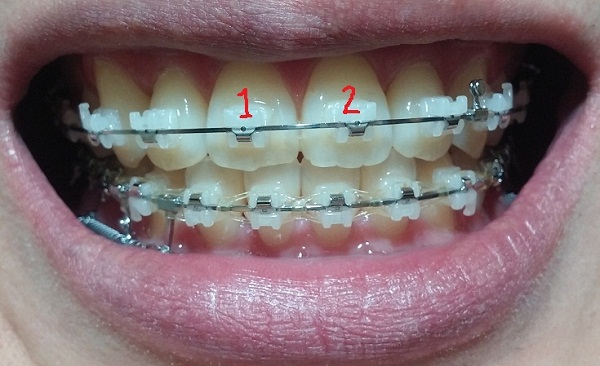

[정면]

-중심선 99% 맞은 상태!!

-하악 파워체인으로 치아끼리 꽉 조여서 마무리로 가는 중!!

-일회용 고무줄로 치아를 다물 때, 뜨는 공간이 없게

상악 송곳니와 하악 송곳니를 당기는 중!!

지금은 다행히 중심선도 다시 맞고 사진을 보시면 아시겠지만 교합이 거의 맞는 듯합니다.